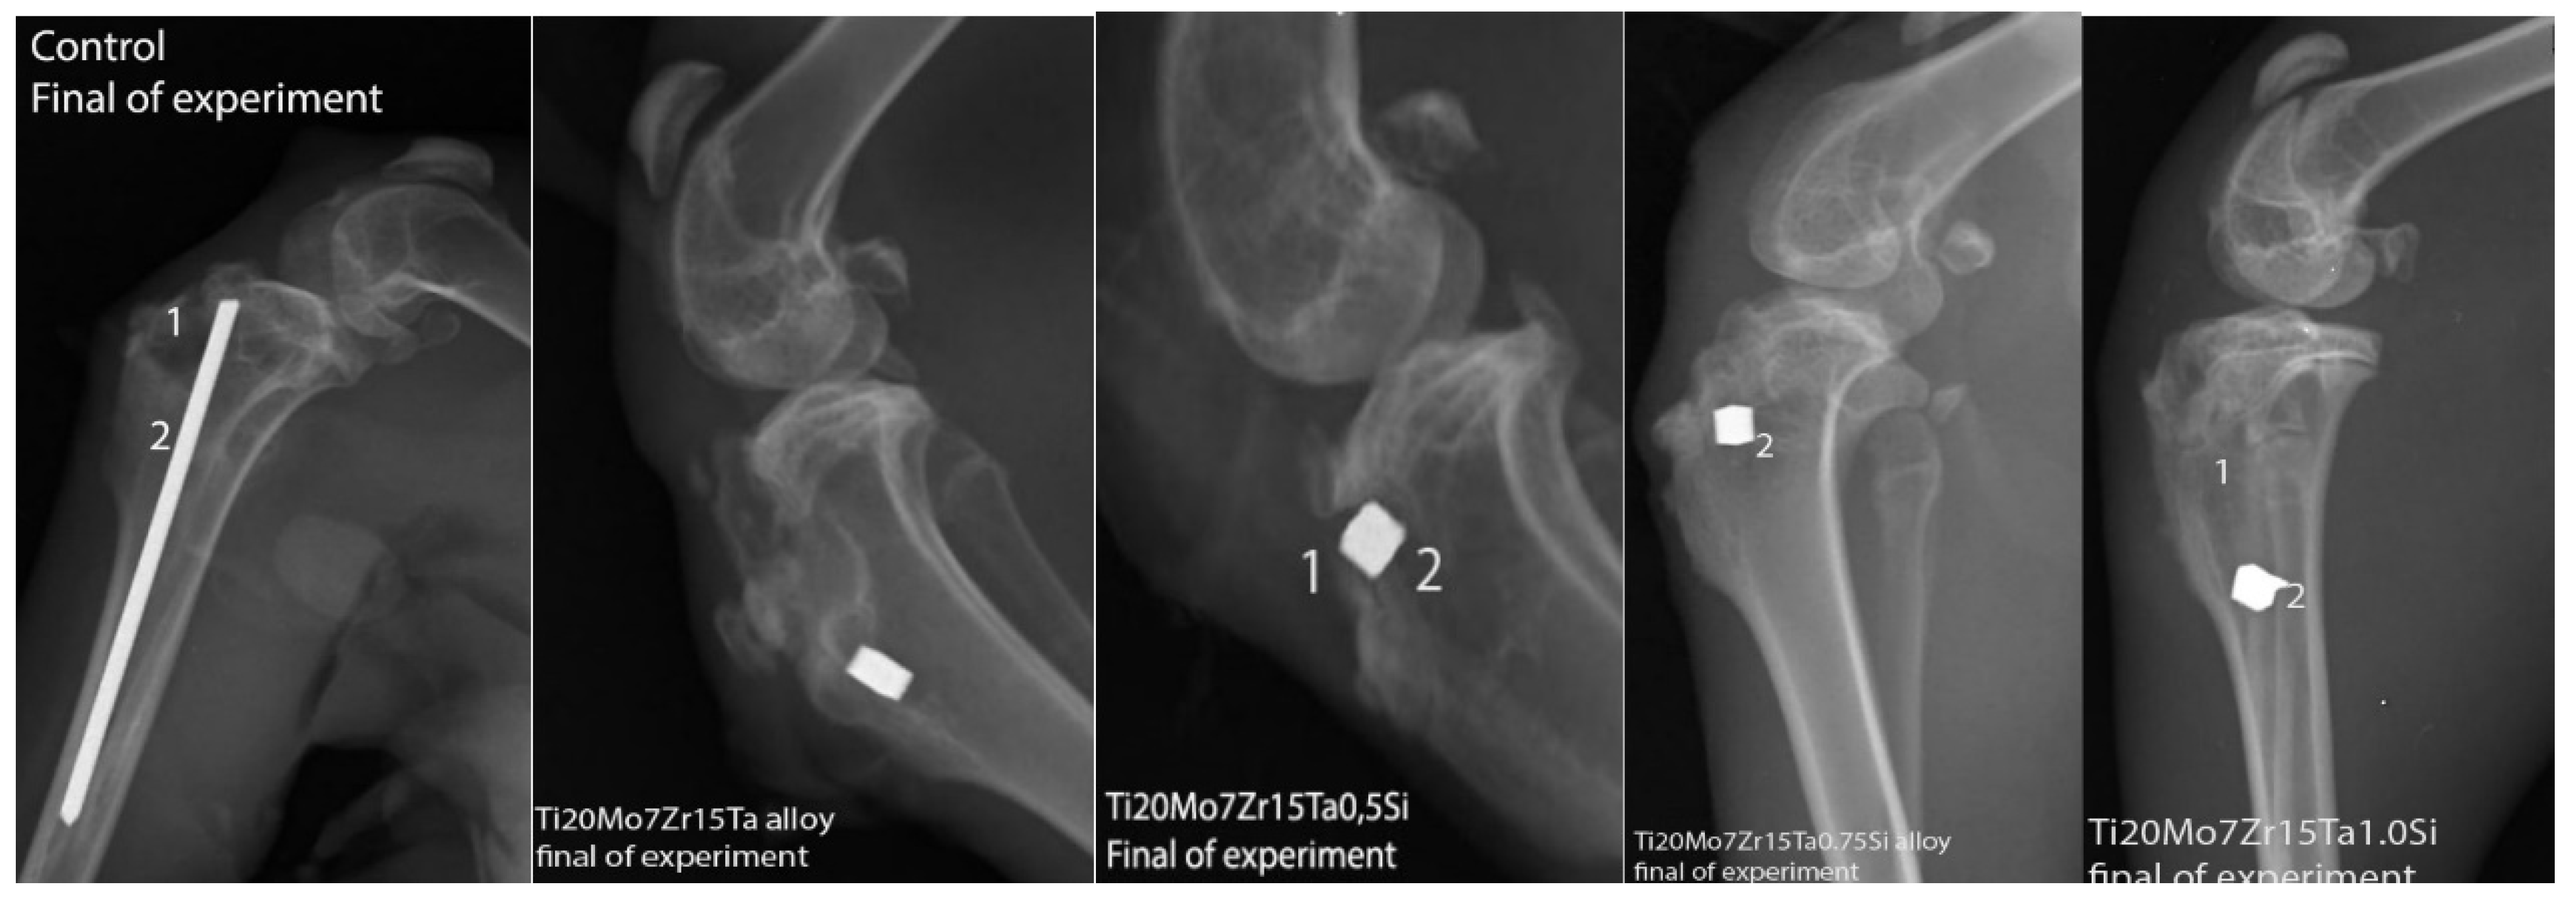

3.4. In Vivo Biocompatibility of Ti-Mo-Zr-Ta-Si Alloys